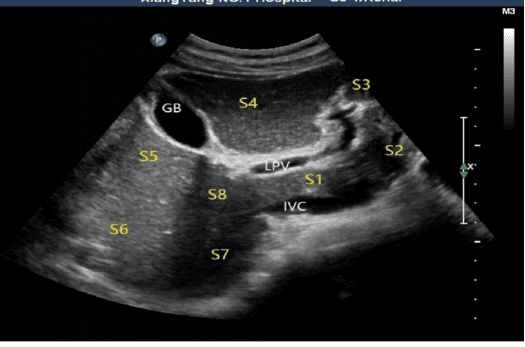

1、腹部亚专业组:腹部超声亚专业组是超声医学领域的重要分支,专注于腹部脏器及相关疾病的超声诊断与评估。专业范畴涵盖肝脏、胆囊、胰腺、脾脏、肾脏、输尿管、膀胱、前列腺等腹部脏器,以及腹腔、腹膜后等区域的疾病诊断。尤其在肝胆胰疾病、泌尿系统疾病及腹部占位性病变的诊断中具有显著优势。

超声造影:通过注射造影剂,清晰显示脏器微血管结构,提高早期肿瘤(如肝癌、胆囊癌)的检出率,精准评估病变性质。